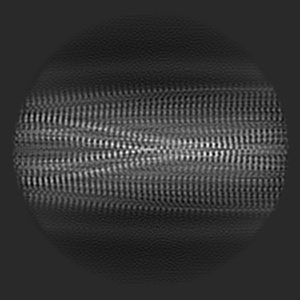

Chronic traumatic encephalopathy tau filaments with PET ligand flortaucipir

Helical reconstruction

2.6 Å

Sample: Sarkosyl-insoluble fraction from the hippocampus of an individual with primary age-related tauopathy

Fitted models: 8byn

Cryo-EM Structures of Chronic Traumatic Encephalopathy Tau Filaments with PET Ligand Flortaucipir.

Shi Y, Ghetti B, Goedert M, Scheres SHW

(2023) J Mol Biol , 435 , 168025 - 168025